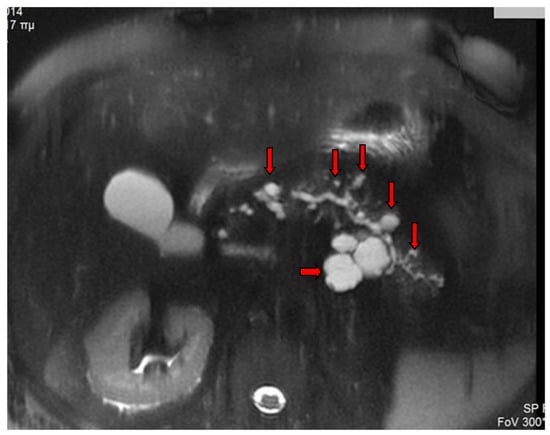

2. Imaging Findings